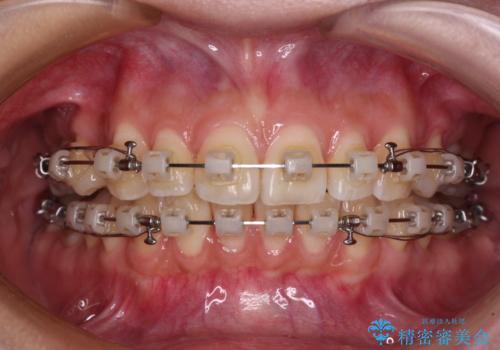

- 矯正装置

- クリアブラケット

- 口を閉じたときに唇の間から飛び出してくる前歯を気にして来院された患者様です。

骨格的に上顎骨が前方位にあるため、左右の第一小臼歯を抜歯し、ワイヤー装置にて咬み合わせを整えていくこととしました。

前歯の突出感が改善されるだけでなく、奥歯の咬み合わせも改善され、食いしばりをしにくい状態に仕上げることができました。